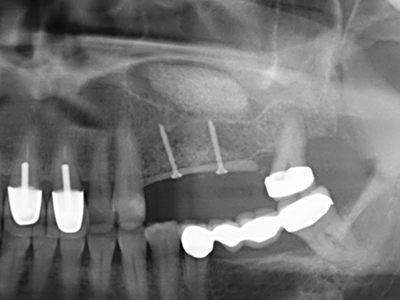

As shown in the past, basically any bone surgery procedure represents a possible indication for piezosurgery. Thus preparation of the mobile segment in distraction osteogenesis (Fig. 23-25) and sandwich osteotomy uses special attachments without endangering the blood supply to the crestal section, which is essential for the success of both techniques (Gonzalez-Garcia, Diniz-Freitas et al. 2008).

For removal of an implant, a vestibular bone cover that is replaced after removal of the implant screw can be prepared to retain the contour of the alveolar ridge.

There are additional applications in sinus surgery. Pathologies and foreign bodies can be removed from the sinus after concentric preparation of a generally trapezoid bone cover in the facial sinus wall. The bone cover is repositioned on conclusion of the intra-antral operation component and secured by wedging or adaptive sutures to prevent dislocation.

Purely orthodontic indications include orthognathic surgery, genioplasty (Fig. 27-30) and orbital decompression in patients with advanced endocrine orbitopathy as a result of Basedow’s disease (Ponto, Zwiener et al. 2014). Piezo devices are also used in maxillofacial surgery and to remove tumours at the base of the skull in various hospitals.